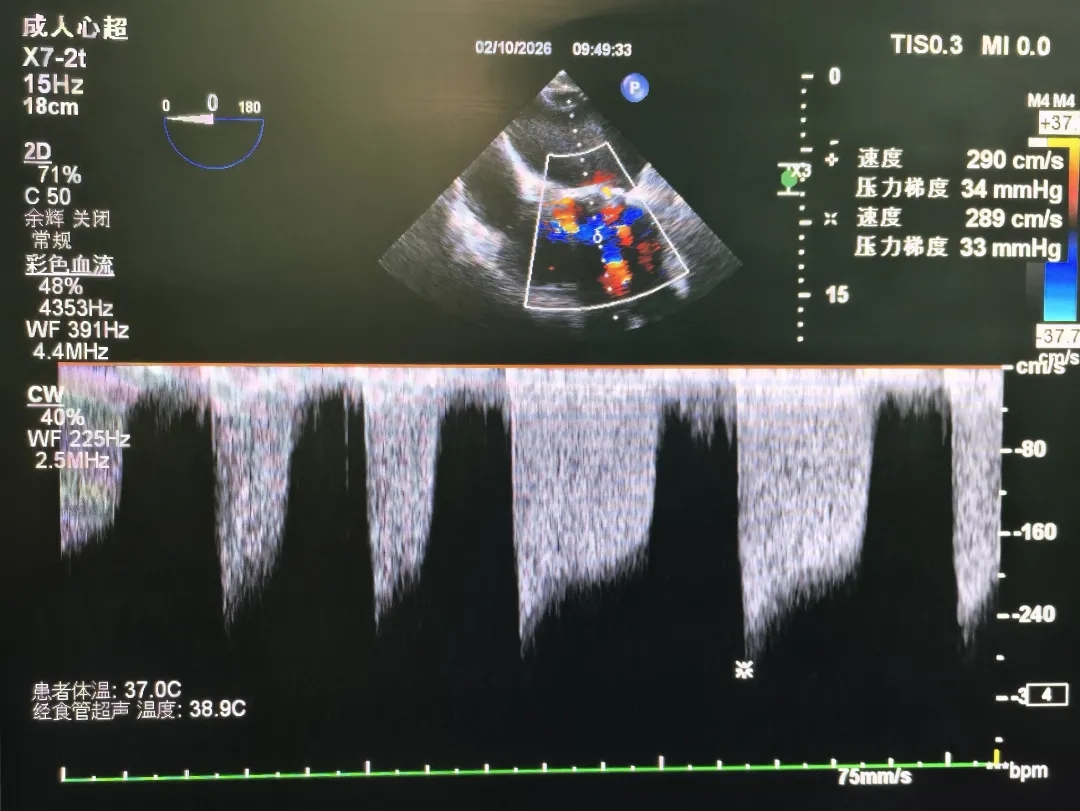

术前超声

左房内血流淤积,二尖瓣可见明显反流束

峰值血流约2.90m/s,峰值压差约34mmHg

术后超声

手术圆满成功,即刻效果显著!

峰值流速:2.90m/s→1.28m/s

峰值压差:34mmHg→8mmHg

瓣周未见明显反流